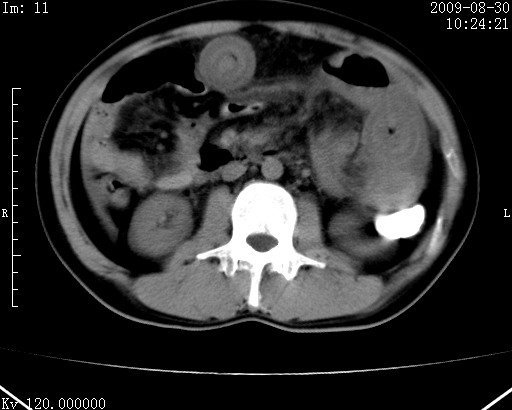

患者唐某,男31岁,已婚,本地务农。

自述入院前两天一次进食较多冷饮之后,出现阵发性上腹部疼痛,次日加剧伴恶心、呕吐,呕吐后症状稍减轻。食欲差。大便每天1-2次,量少,暗红色水样。小便赤。无畏寒、发热、咳嗽等呼吸道症状。无高血压及胃病史。

检查:体温、血压及脉搏正常.皮肤无黄染,浅表无淋巴结肿大。左腹肌紧张,左上腹有压痛,无反跳痛,可触及包块。

生化:钾、钠、氯、钙、ph正常,总胆红素和直接胆红素稍高,空腹血糖稍高。

尿淀粉酶:1256 u/l(正常60-401)。

血常规:wbc 22.4x109/l gr88% ly9.6%其余基本正常。

胃镜:急性胃炎。立位腹平片:未见异常。

下面是ct平扫,降结肠内是对比剂。

术前影像诊断:上段空肠急性缺血性坏死并腹水。建议手术治疗。

术中见上段空肠约70cm长范围坏死,从屈氏韧带远端约10cm处开始。坏死肠管肿胀变形变色,管壁明显环形增厚,部分聚成大肿块,无扭转和套叠。肠系膜上动脉分支内广泛泥沙状血栓。肠切除。

临床诊断:肠系膜上动脉梗塞并急性肠坏死。

开始时我们科也有人认为是套叠,最后统一意见,不考虑肠套。我们看到的“靶征”,“晕圈征”,“双圈征”实际上只是单根肠管的横断面。坏死肿胀后肠壁各层的密度不一样。

左侧腹小肠腔管壁明显增厚,部分内示靶征,走行异常,部分肠系膜绳样改变,肝包膜下及肠间较多液体密度,然梗阻近端肠腔积气不明显。

考虑;肠扭曲伴肠坏死。